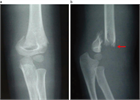

1. X線、CT、MRIなどの画像診断やエコーは病変の局在、程度を知るために重要である。